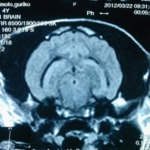

画像は9歳のゴールデンレトリーバーの頭部MRIです。本症例は発作を主訴に来院されました。

MRI検査の結果、前頭葉に脳腫瘍が確認されました。